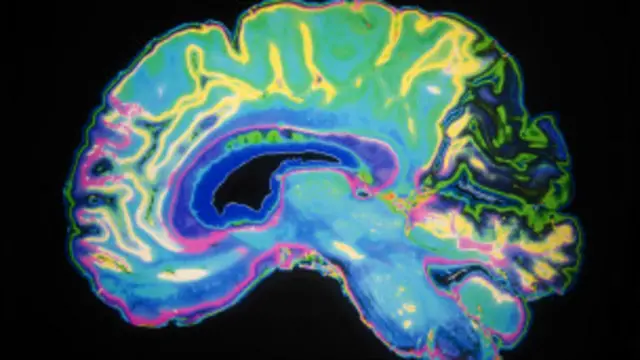

Perubahan memori dan konsentrasi yang dialami Lily menyusul perawatan kankernya disebut dengan "otak kemo" atau "kabut kemo."

Cancer Research Inggris menyebut gejala ini sebagai "otak kemo" yang ditandai dengan melupakan hal-hal yang biasanya diingat, sulit memikirkan kata yang tepat dan bingung jika mengikuti pembicaraan.